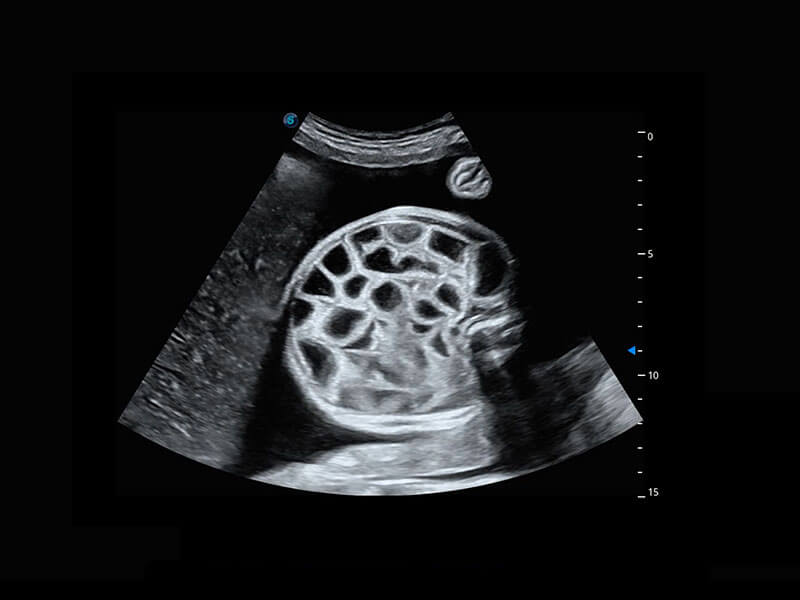

P60在胎儿早孕期超声筛查中为您带来优异的图像质量。

早孕-胎心

高分辨率容积成像-早孕胎儿

胎儿体循环

光影成像-孕囊